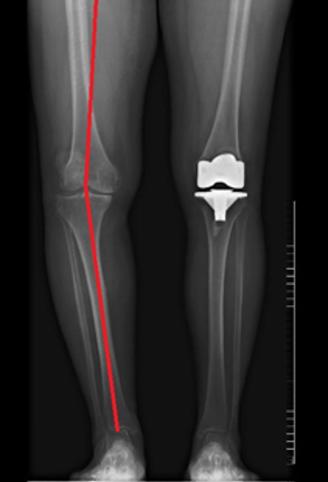

术后X片

髋-膝-踝角180°(理想值180°)

手术完美恢复下肢力线

术前双下肢全长X片

髋-膝-踝角169°

(内翻11°)